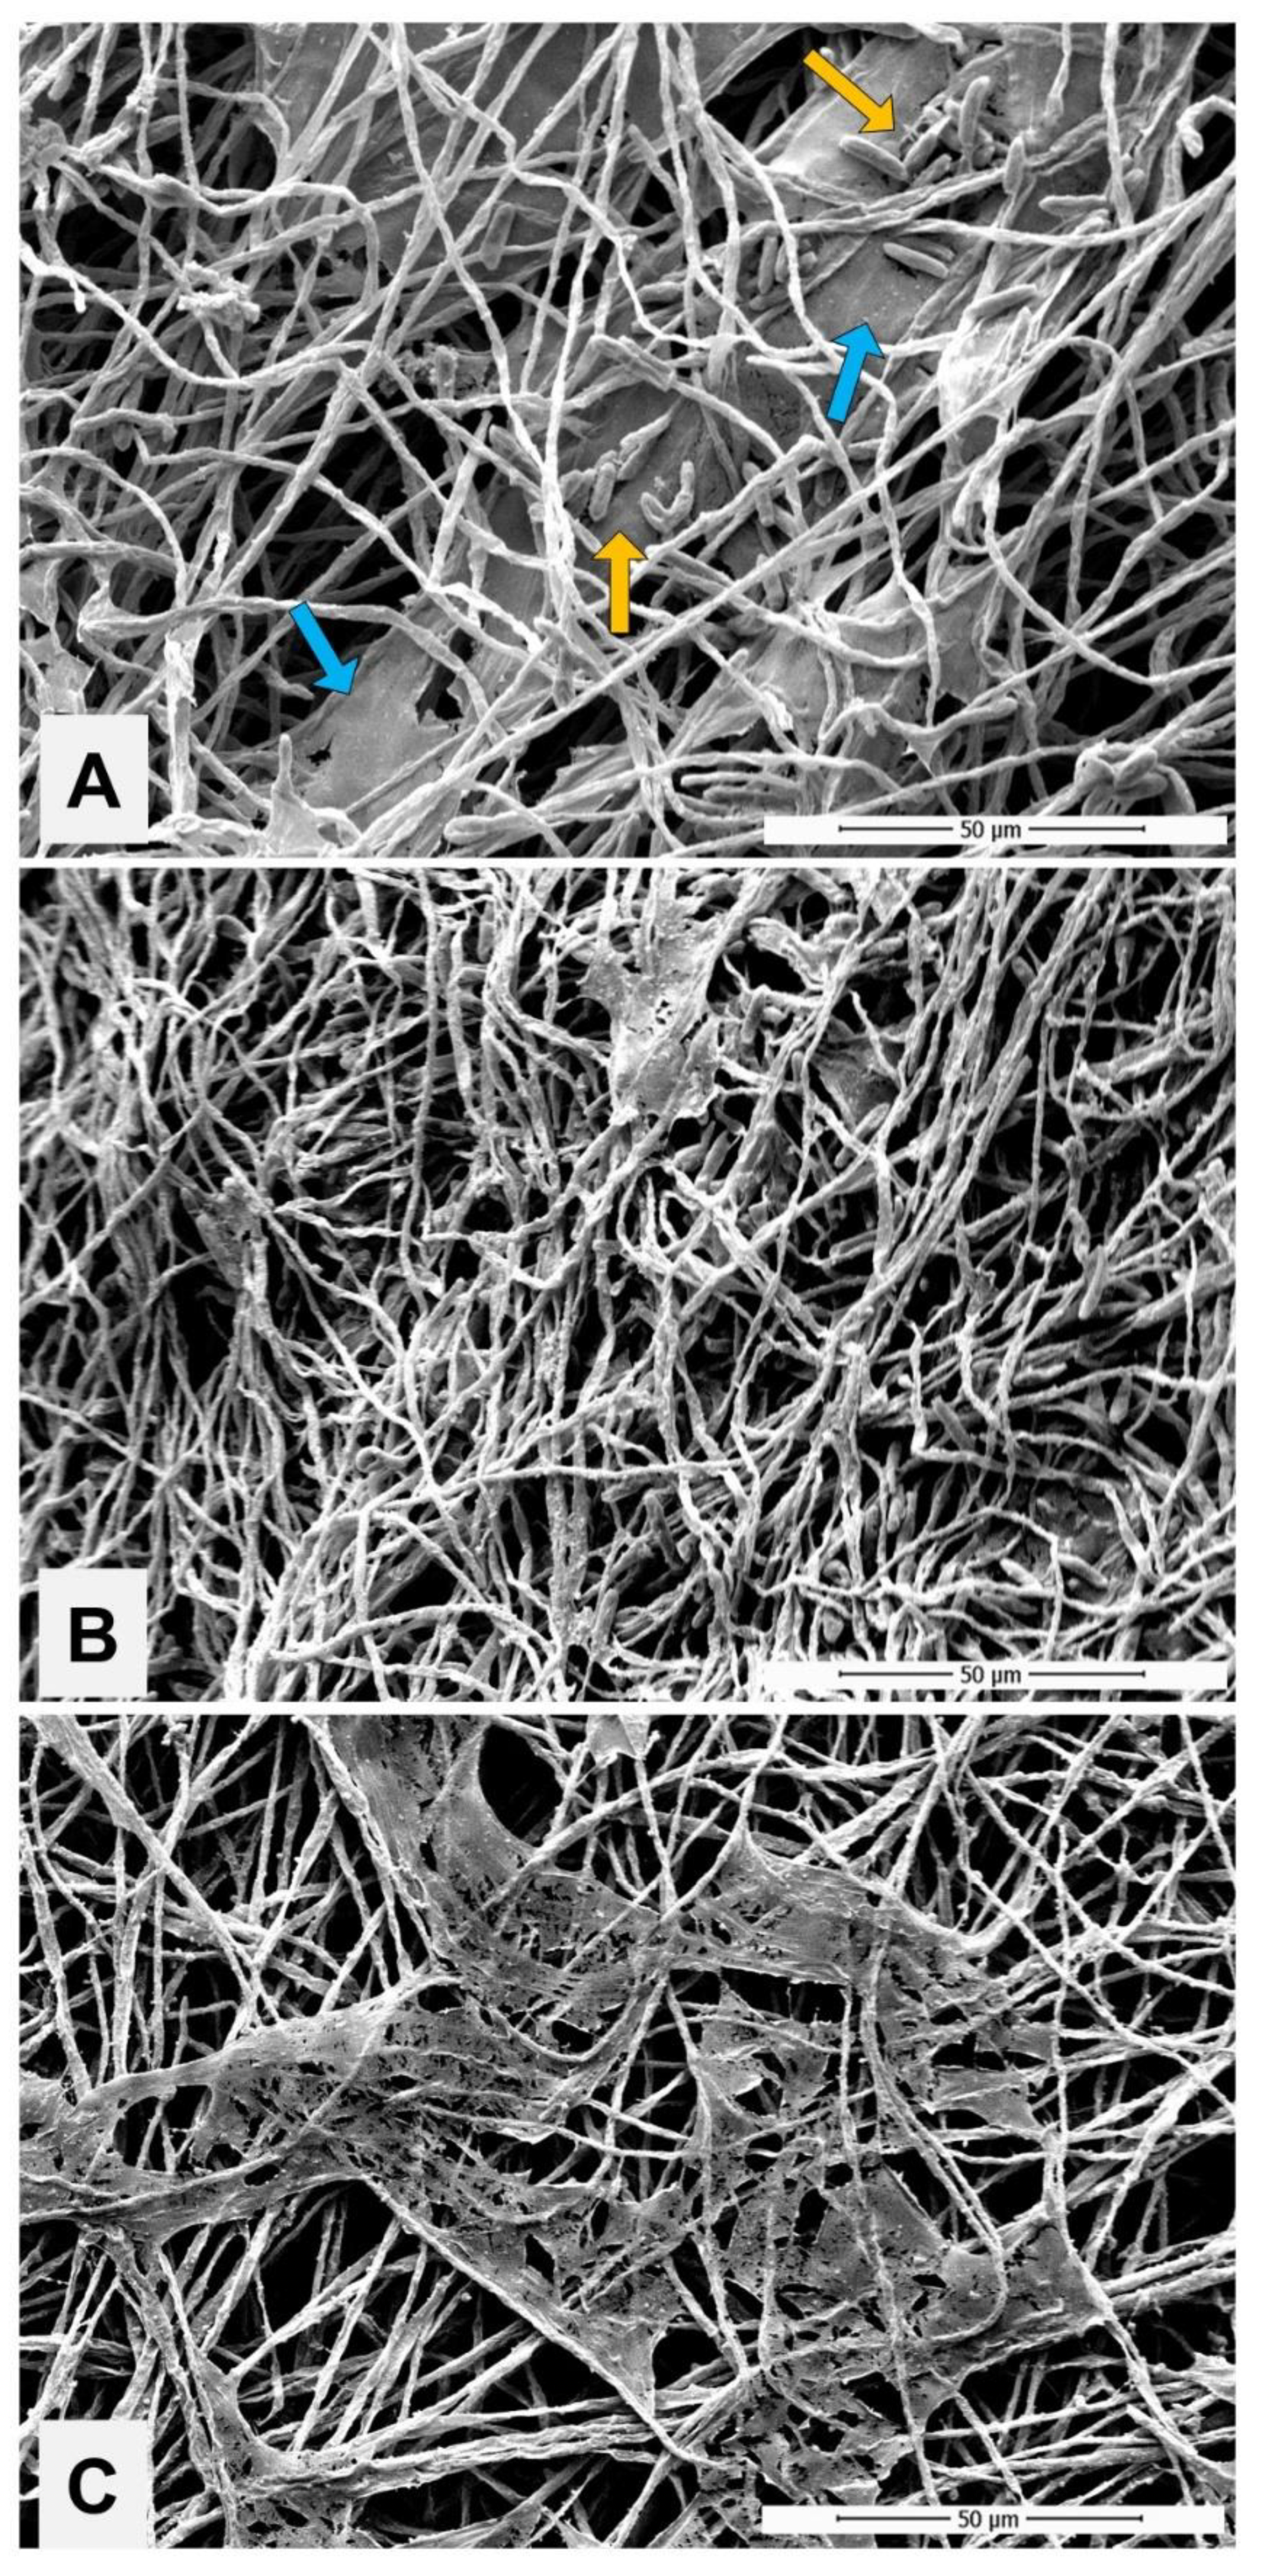

2.4.3. Impact of PE Exposure to the Biofilm